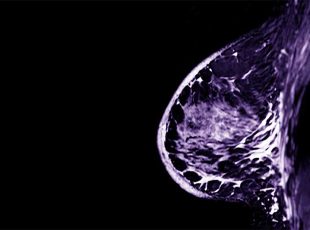

L’ecografia mammaria a Catenanuova impiega sonde ad alta frequenza (≥ 10 MHz), garantendo un’accurata valutazione del tessuto mammario. Questo esame non invasivo è privo di radiazioni ionizzanti, rendendolo sicuro e ripetibile. Viene spesso utilizzato come completamento della mammografia per ottenere una diagnosi più completa e dettagliata.